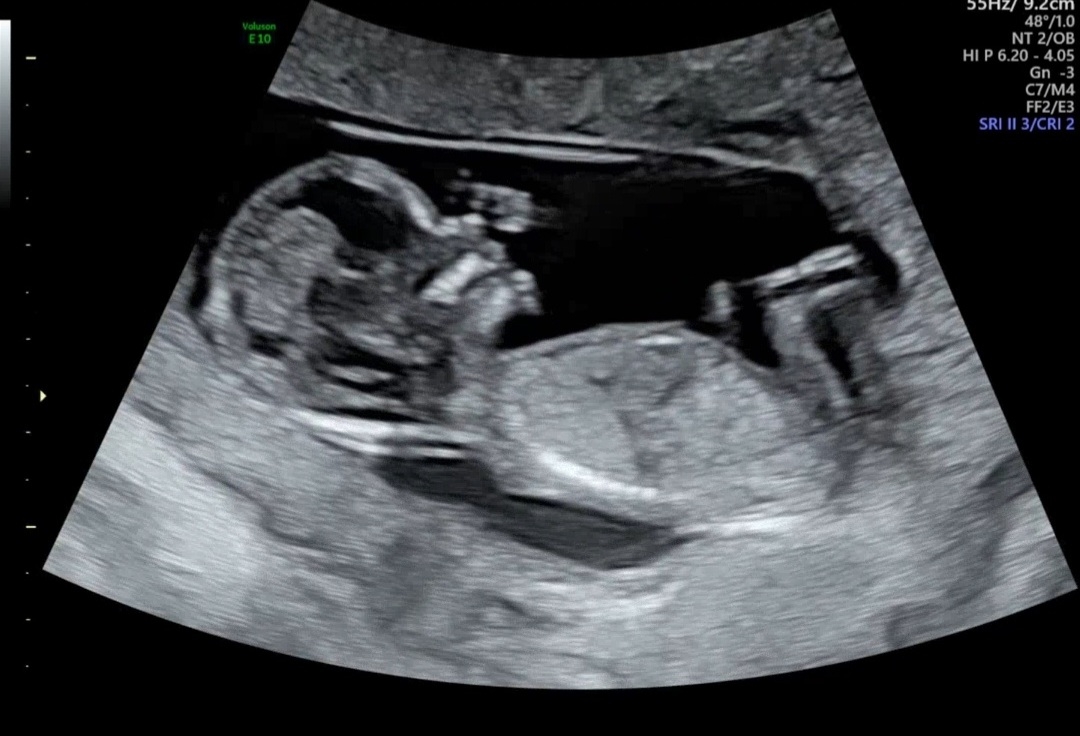

12주6일차 각도법 한번 봐주세용😆💖

12주6일 첫 기형아 검사했는데 이사진으로도 각도법 볼수있을까여!?😆